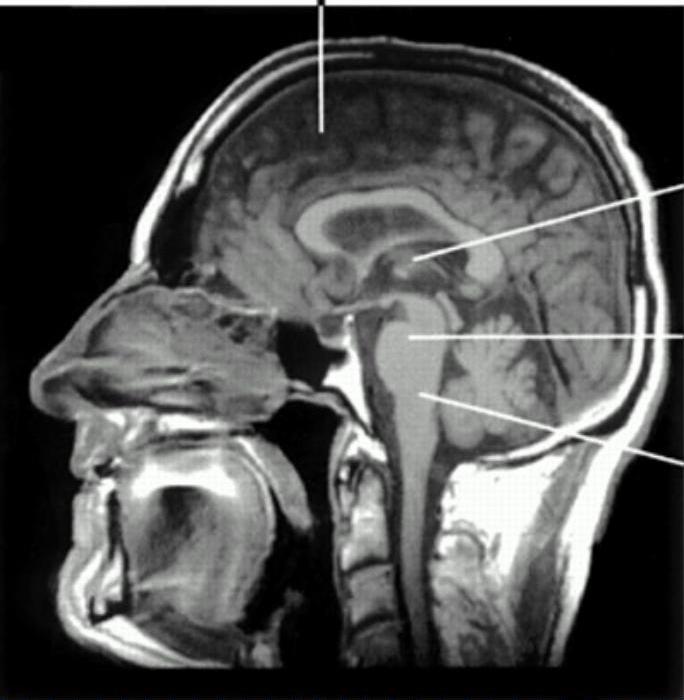

ASCENDING RETICULAR ACTIVATION SYSTEM

Ascending reticular activating system

Arousal depends on an intact:

a) ascending reticular activating system

b) connections with diencephalic structures